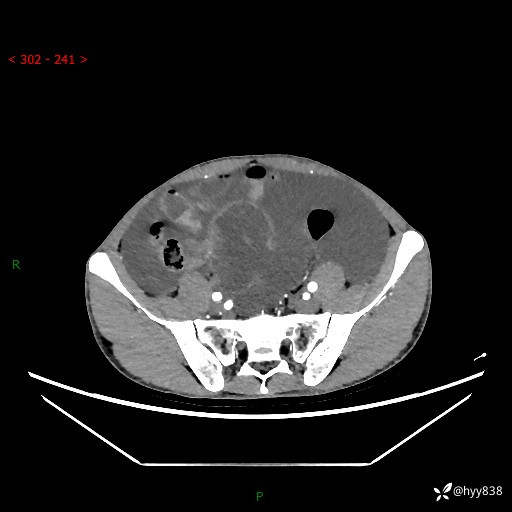

现病史:患者10天前无明显诱因出现腹部胀痛不适,无畏寒发热,无胸痛胸闷,无心慌气短,无恶心呕吐,无腹泻及黑便,无粘液血便及里急后重等症状,4天前在当地县人民医院就诊,行腹部CT示:下腹部占位性病变,腹腔及盆腔积液;今患者为求进一步诊治来我院治疗,门诊以“腹水”收治入院。 发病以来,精神饮食可,大小便正常,体重体力无明显变化。

腹部CT平扫+增强